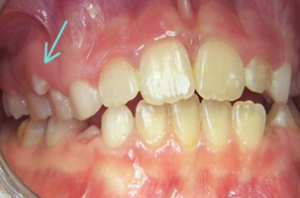

Hình dạng răng (răng sinh đôi, răng dính, sinh hợp..) cũng có thể là nguyên nhân gây lệch lạc răng. Những sai lệch nặng về hình dạng, kích thước răng là nguyên nhân thường gặp gây ra sai khớp cắn răng mặt.

Một trường hợp răng đôi (răng dính)